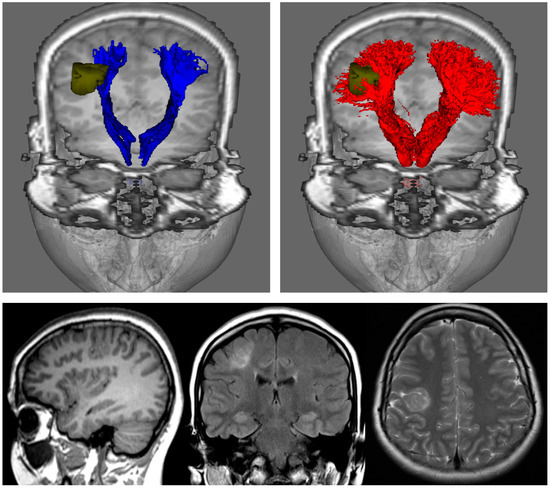

Figure 3.

Fibre-tracking results on a 24-year-old woman with a right focal cortical dysplasia situated in the right posterior frontal lobe (see images in bottom row). These results were obtained using a seed region in the brainstem and target regions in the sensorimotor cortices. DTI-based tractography (blue) and CSD-based tractography (red) were derived from the same diffusion MRI data set); segmented pathology volumes (green) overlaid on T1-weighted image. DTI-based tractography suggests that only the medial aspect of the lesion impinges on the corticospinal tracts, whereas CSD-based tractography suggests that the lesion is enveloped by medial and lateral projections. DTI: Diffusion Tensor Imaging; CSD: constrained spherical deconvolution. Note that while only DTI combined with deterministic tracking is shown in the top-left image, the results of combining DTI with probabilistic tracking are expected to be very similar (cf. left and middle images in Figure 2). Figure modified from a figure previously published in [30], with permission of American Association of Neurological Surgeons, 2013.